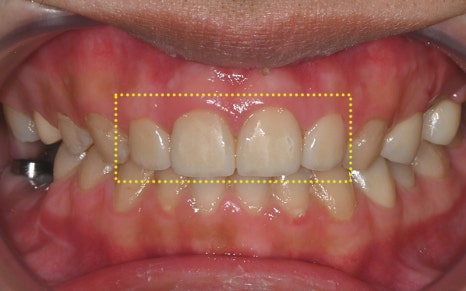

하지만 치료 후 사진은

완전히 다른 사람이 된 듯한 변화가 느껴집니다.

마치 원래부터 예쁘고 반듯했던 치아처럼,

색상도 자연스럽고

모양도 얼굴형에 딱 맞게 복원되었습니다.

실제로 환자분께서는

“이게 진짜 원래 내 치아 같고,

치료한 티가 하나도 안 난다”며

만족을 표현해주셨고,

“예전에는 항상 소극적이었는데,

요즘은 사람들 앞에서 활짝 웃게 된다”고

말씀해주셨답니다.

저희가 추구하는 ‘자연스러움 속의 심미성’을

가장 잘 보여주는 결과였습니다.

💛 전 > 후 💛

2025.01.05

▼▼▼▼▼

2025.05.21